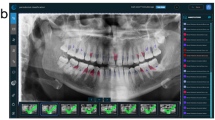

This study used a balanced dataset [26]. Images from the case and control group datasets were randomly assigned to one of three datasets: a training set of 1,370 images, a validation set of 150 images, and a test set of 150 images. The training and validation datasets were used to train a Faster R-CNN [32, 33]. Subsequently, the dentist with more than 5 years of clinical experience (reference standard) drew a rectangular bounding box around the dental implants and crowns, and around areas of marginal bone loss surrounding implants (ground truth bounding box for the case group). Another oral and maxillofacial radiologist confirmed the initial bounding box positions. During annotation, the clinicians drew the smallest possible bounding box around each area of marginal bone loss surrounding the implants in each image (Fig. 1).

“Keypoints” for marginal bone loss assessment. a platform switch implant; b platform match implant. Red points indicate coronal keypoints; green points indicate apical keypoints. For platform-switched implants, the coronal keypoints were located on top of each implant. For bone-level platform-matched implants, the coronal keypoints were located on the bottom of the implant neck. The apical keypoints comprised the first point of contact between the bone and implant. The yellow bounding boxes denote areas of marginal bone loss

For platform-matched implants, the bottom of the implant neck near the most coronal thread was considered as the top of the implant [7]. For platform-switched implants, the most coronal edge was considered as the top of the implant [14]. The apical “keypoints” were the first contact points of the bone and implant. Coordinates in the image were set in accordance with the distance from the top-left corner. The bounding box was described in terms of its top left and bottom right corners (xmin, ymin; xmax, ymax).

Table 2 provides information on the implants in the training and test datasets. As shown in Fig. 3, although some diagnoses were missed, the bone loss area detected by Faster R-CNN was generally similar to the ground truth bounding box. With increasing severity of bone loss, the Faster R-CNN model and observer annotations converged.

The impact of implant-supported prosthesis type on peri-implant bone loss and peri-implantitis remains unclear [7, 40]. The differential effects on loss of marginal bone between platform-matched and -switched implants has received increasing attention in recent years; a meta-analysis by Chrcanovic et al. [41] suggested that significantly less marginal bone loss occurs with the latter type of implant. Dentists must distinguish the abutment-implant connection type and appropriate reference points when analysing radiographs for marginal bone loss around dental implants. Platform-switched level implants should maintain marginal bone stability at a level equivalent to the top of the implant [14]. Platform-matched implants have a smooth neck, and the marginal bone should be stabilised at the junction between the smooth and rough implant surfaces [42]. In this study, we divided the marginal bone loss training data according to the implant-abutment connection type, and the bone resorption areas automatically identified by the CNN were generally consistent with these classifications (Fig. 3). These findings differed from those of Cha et al. [28], whose dataset included various implants with different implant-abutment junctions. In that study, the most coronal thread of the implant was used as a threshold position.

According to the VIII European Workshop on Periodontology [43], radiographs of implants are recommended after physiological remodelling (generally at the time of prosthesis fitting) to assess changes in the level of crestal bone. These baseline radiographs were unavailable for some patients in our dataset. Exposure of the rough implant surface can serve as an indicator of bone resorption around the implant. In this study, bounding boxes were used for qualitative detection of marginal bone loss (Fig. 2). The Faster R-CNN model was used in this study for feature detection and classification, while Cha et al. [28] used a Mask R-CNN model that detects and classifies targets by drawing target frames, and then segments targets at the pixel level. However, the cost of training is considerable because a set of keypoints must be precisely annotated for model training; also, specialised equipment is needed for training [34].